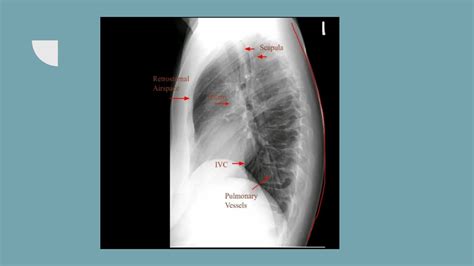

Interpreting a Lateral Chest X Ray requires a trained eye and knowledge of normal anatomy. Key structures to assess include:

• The heart and its borders

• The lungs and any visible abnormalities

• The diaphragm and its position

• The ribs and spine

• lateral chest x ray labeled